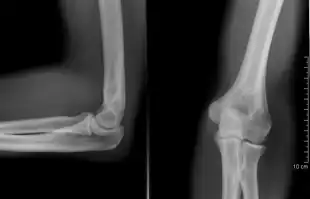

Right: AP X ray of a dislocated right elbow

There are three bones at the elbow joint, and any combination of these bones may be involved in a fracture of the elbow. Patients who are able to fully extend their arm at the elbow are unlikely to have a fracture (98% certainty) and an X-ray is not required as long as an olecranon fracture is ruled out.[27] Acute fractures may not be easily visible on X-ray.[28]

Dislocation

Elbow dislocations constitute 10% to 25% of all injuries to the elbow. The elbow is one of the most commonly dislocated joints in the body, with an average annual incidence of acute dislocation of 6 per 100,000 persons.[30] Among injuries to the upper extremity, dislocation of the elbow is second only to a dislocated shoulder. A full dislocation of the elbow will require expert medical attention to re-align, and recovery can take approximately 6 weeks.